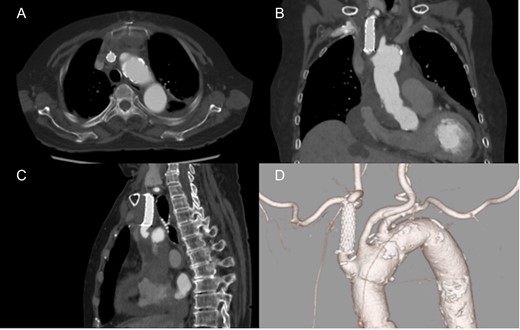

An 82-year-old woman with loss of consciousness was transferred to our institution. CT showed aortic dissection involving ascending aorta extending to the brachiocephalic artery where the true lumen was occluded due to the false lumen. The level of consciousness was getting improved during examination, then, the decision was made to proceed with performing central aortic repair first. Cardiopulmonary bypass was established with ascending aortic and bicaval cannulations. Through the surgery, rSO2 was continuously within normal range bilaterally. Incising the aorta, the tear was located in the ascending aorta and the brachiocephalic artery was severely compressed by the false lumen. Then, the lesion was expanded and stabilized with the S.M.A.R.T. stent (10 mm × 40 mm) (Fig. 3). Finally ascending aortic replacement by using 26 mm J-Graft was done. The neurological status was clear after the surgery. There were no neurological or stent induced complications at discharge and the most recent follow-up.